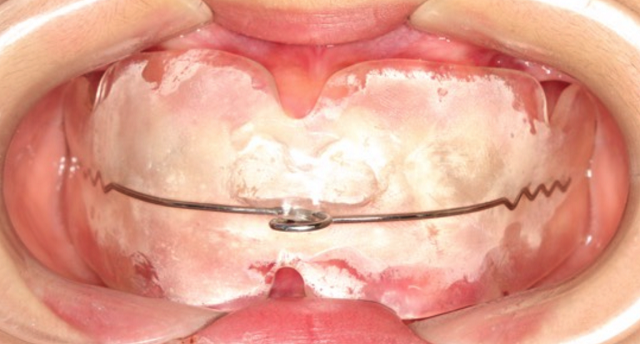

黃丞一副主任醫(yī)師仔細(xì)檢查后發(fā)現(xiàn),孩子的門牙突出,上頜牙弓特別狹小,整排牙齒都非常不整齊。

“當(dāng)腺樣體組織異常增生肥大時(shí),就會(huì)堵塞氣道,導(dǎo)致長(zhǎng)期張口呼吸,還可影響頜面部發(fā)育,形成特殊的腺樣體面容。腺樣體面容是指由于腺樣體肥大導(dǎo)致牙齒不整齊并且向外凸出,形成齙牙,上嘴唇也會(huì)變厚,腭骨高拱,還伴有表情呆滯等情況。”黃丞一醫(yī)生說(shuō)。

雖然當(dāng)時(shí)接診時(shí),小林的腺樣體腫大已經(jīng)存在了一段時(shí)間,不過(guò)幸好發(fā)現(xiàn)及時(shí)。根據(jù)黃醫(yī)生的建議,小林及時(shí)到耳鼻喉科做了腺樣體摘除術(shù),并且認(rèn)真地進(jìn)行肌功能訓(xùn)練,對(duì)已經(jīng)凸出的牙齒進(jìn)行矯正。

第三,如果已經(jīng)發(fā)生了口腔錯(cuò)合畸形,就需要根據(jù)不同的錯(cuò)合畸形類型進(jìn)行功能性矯正和后期的固定矯正了。